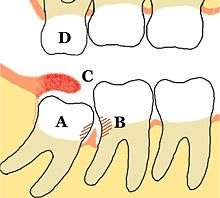

Wisdom teeth (often notated clinically as M3 for third molar) have long been identified as a source of problems and continue to be the most commonly impacted teeth in the human mouth. The oldest known impacted wisdom tooth belonged to a European woman of the Magdalenian period (18,000–10,000 BCE).[5] A lack of room to allow the teeth to erupt results in a risk of periodontal disease and dental cavities that increases with age.[6] Less than 2% of adults age 65 years or older maintain the teeth without cavities or periodontal disease and 13% maintain unimpacted wisdom teeth without cavities or periodontal disease.[7]

Impacted wisdom teeth are classified by the direction and depth of impaction, the amount of available space for tooth eruption and the amount soft tissue or bone that covers them. The classification structure allows clinicians to estimate the probabilities of impaction, infections and complications associated with wisdom teeth removal.[6] Wisdom teeth are also classified by the presence of symptoms and disease.[8]

Treatment of an erupted wisdom tooth is the same as any other tooth in the mouth. If impacted, treatment can be localized to the infected tissue overlying the impaction,[9]:440–441 extraction[10] or coronectomy.[11]